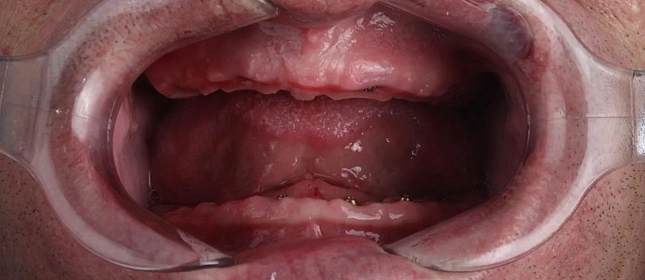

Лечение аномалии соотношений зубных дуг на брекет-системе

Лечение прикуса и восстановление эстетики винирами